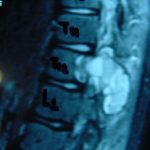

Εικ. 3: Μαγνητική τομογραφία α-στ Οβελιαία (Saggital) λήψη ακολουθία Τ1-Τ2, ζ-ιβ Εγκάρσια (Axial) λήψη ακολουθία Τ1-Τ2

Παρατηρείται ευμεγέθης εξεργασία στα οπίσθια στοιχεία του Θ12 σπονδύλου η οποία προκαλεί διόγκωση των δομών , λέπτυνση του φλοιού, χωρίς σημάδια διάσπασης του φλοιού. Η εξεργασία προβάλλει και στενεύει το σπονδυλικό σωλήνα, ενώ προκαλεί πίεση του νωτιαίου μυελού. Δεν αναγνωρίστηκαν παθολογικά ευρήματα από τον έλεγχο των σπονδυλικών σωμάτων και των μεσοσπονδύλιων τμημάτων της ΟΜΣΣ.